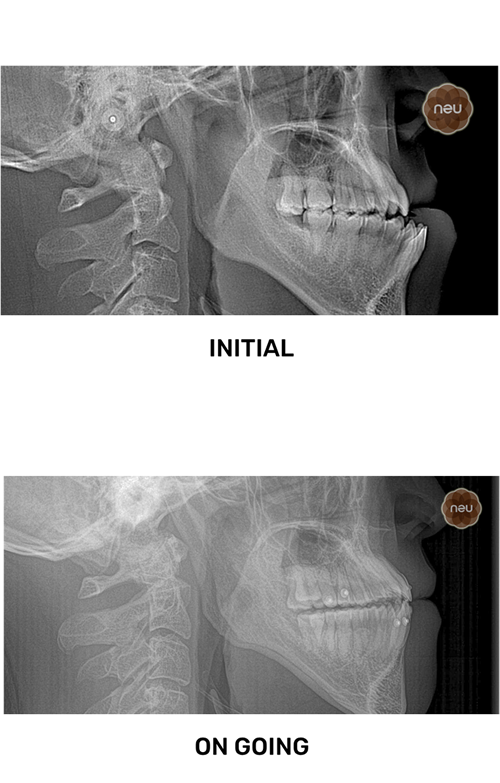

THE CHALLENGE

Usually, a reversed bite affects looks and function.

But at Neu, we correct it with precise, customized treatment.

Usually, complex bite corrections take time.

But at Neu, we use digital planning and bite simulations to guide each step with precision.